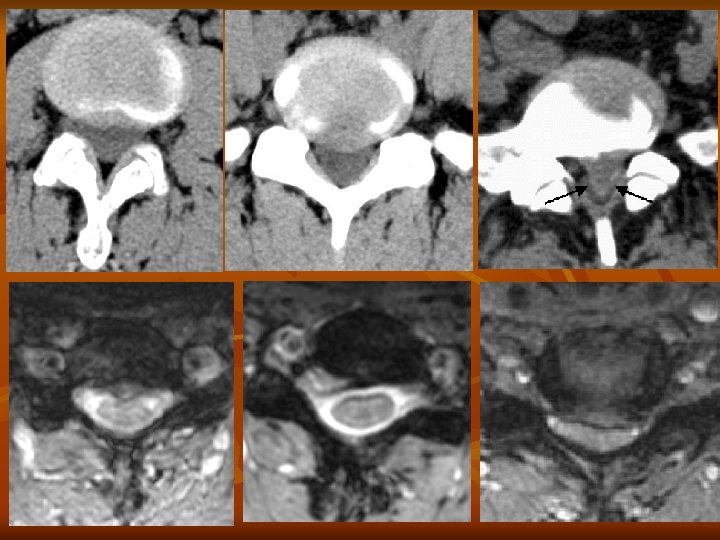

Hernia (porckorongsérv) n n A belső mag (nucleus pulposus) a fibrózus külső gyűrűn keresztül (annulus fibrosus) előboltosul. Az annulus fibrosus szakadása a hernia helyén fájdalmat okoz Hernia tipusok: n n n n Szétterült korong Discus protrusio Prolapsus Szekveszter (kiszakadt sérv) Éles, metsző fájdalom Izomerő és érzészavar a neurológiai vizsgálat során, reflexeltérések MR CT

Hernia fokozatok